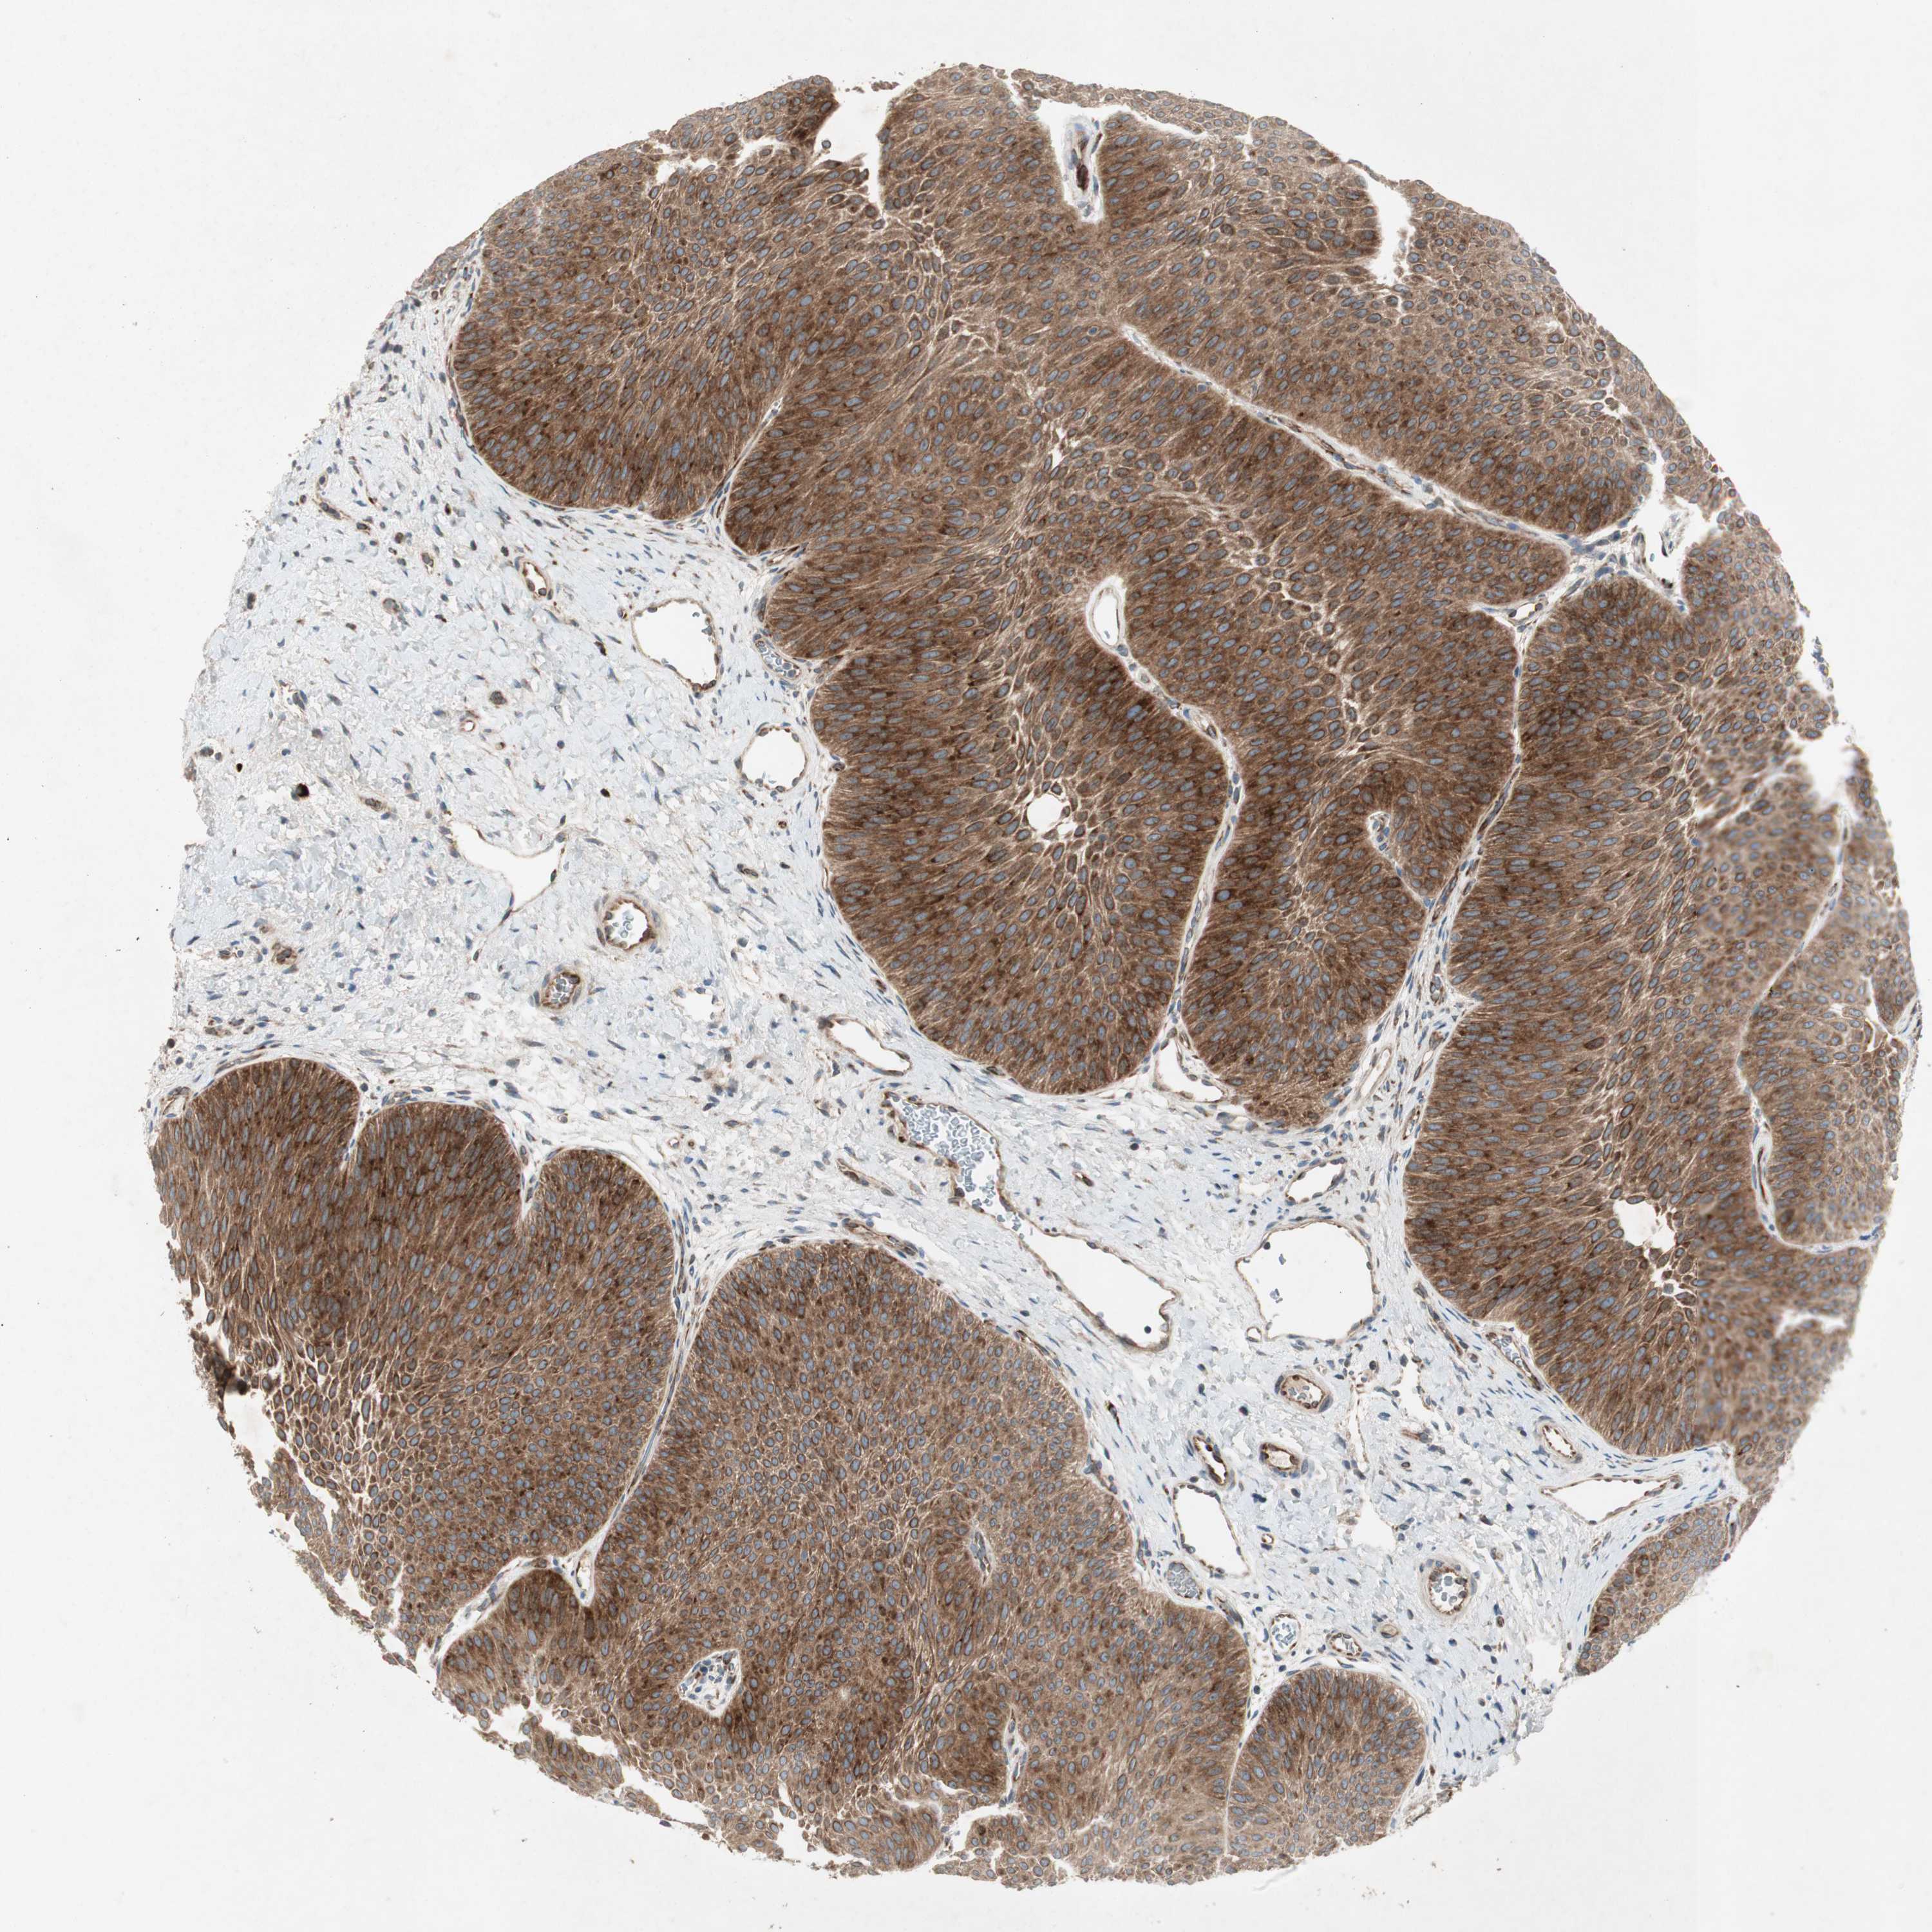

UROTHELIAL CANCER - Protein expressioni

A mouse-over function shows sample information and annotation data. Click on an image to view it in a full screen mode. Samples can be filtered based on level of antibody staining by selecting one or several of the following categories: high, medium, low and not detected. The assay and annotation is described here.

Note that samples used for immunohistochemistry by the Human Protein Atlas do not correspond to samples in the TCGA dataset.

Antibody stainingi

Antibody staining in the annotated cell types in the current human tissue is reported as not detected, low, medium, or high, based on conventional immunohistochemistry profiling in selected tissues. This score is based on the combination of the staining intensity and fraction of stained cells.

Each image is clickable and will lead to virtual microscopy that enables deeper exploration of all samples and also displays staining intensity scores, fraction scores and subcellular localization as well as patient and tissue information for each sample.

Antibody HPA003187

Staining

High

Medium

Low

Not detected

Intensity

Strong

Moderate

Weak

Negative

Quantity

>75%

75%-25%

<25%

None

Location

Nuclear

Cytoplasmic/membranous

Cytoplasmic/membranous,nuclear

Urothelial carcinoma, Low grade

Urothelial carcinoma, High grade